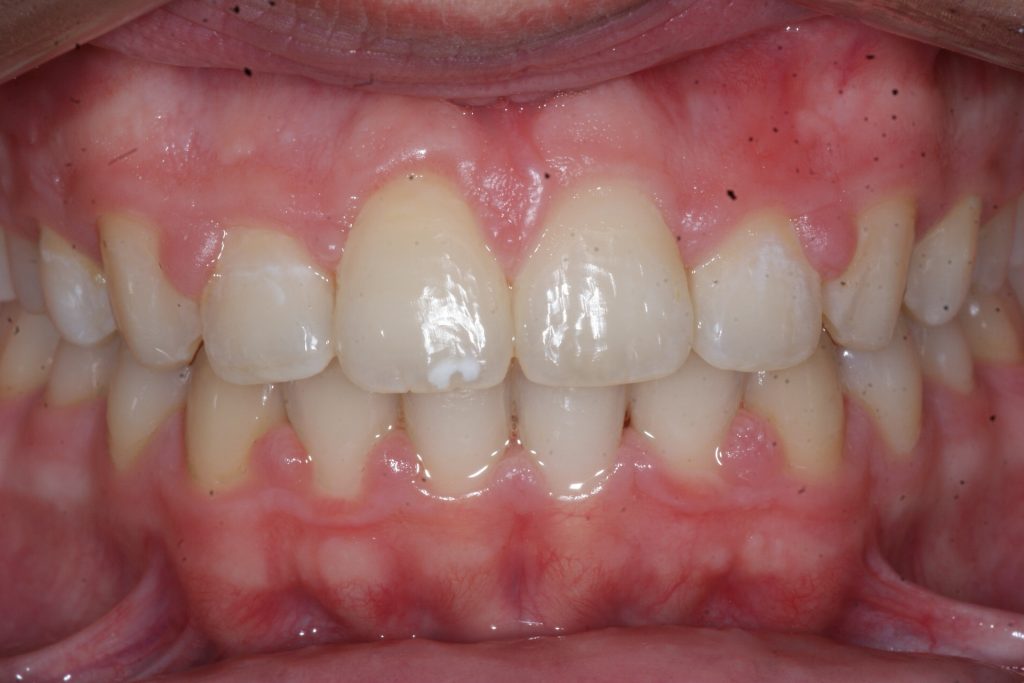

Correction d’une malocclusion de type Classe II.  Des appareils fixes (boîtiers) et une expansion palatine furent nécessaires pour améliorer ce sourire.  Traitement chez un adolescent, réalisé en 21 mois.